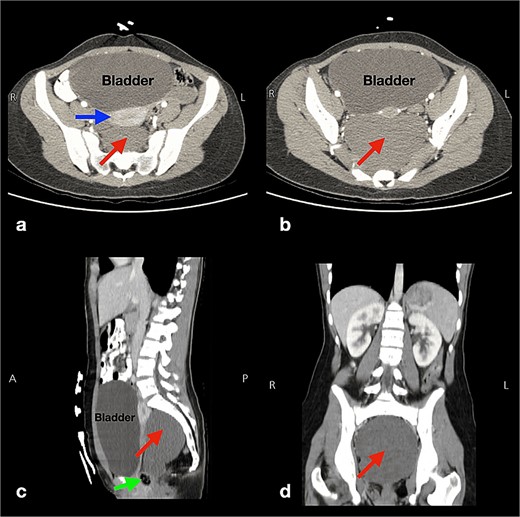

She underwent a thorough physical examination. Her abdominal examination was unremarkable. Her digital rectal exam revealed a painless posterior rectal bulge with smooth overlying rectal mucosa. Therefore, she underwent an abdominopelvic computed tomography (CT) scan with intravenous (IV) contrast, which revealed a well-defined binoclulated cystic mass, without a soft tissue component nor calcification, measuring 11 × 10.5 × 8 cm (red arrows in Fig. 1a–d). It is located in the presacral region, in intimacy with the sigmoid colon, rectum (green arrow in Fig. 1c), ureters anteriorly (blue arrow in Fig. 1a), with both of the iliac vessels located laterally. The bladder was also severely distended (Figs. 1a–c).

Multi-plane (a,b: axial and c: sagittal, d: coronal) abdominopelvic computed tomography scans displaying a well-defined cystic lesion, with fluid attenuation, and of biloculated nature measuring 11 × 10.5 × 8 cm (arrows in pictures a, b, c, d). This lesion has no soft tissue components or calcifications and is located in the presacral region near the sigmoid colon, rectum (arrow in picture c), and the uterus anteriorly (horizontal arrow in picture a), and both iliac vessels laterally. Also, the bladder is severely distended (pictures a, b, c).